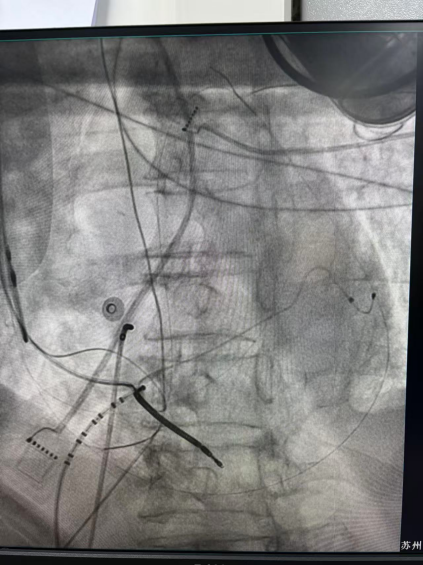

一般来说,扩张型心肌病患者的心肌病变常位于中外膜,往往需要内外膜联合消融,但此例患者伴有慢性肾衰,凝血功能差,因此,干性心包穿刺风险较大。为解除患者的痛苦,陈弹主任医师和王林林主任医师带领电生理团队决定为患者施行室速射频消融术。

干穿心包进入外膜标测

心外膜基质

王林林主任医师谨慎操作,成功进入心外膜达到病变位置。术中,患者反复自发多形态室速,且转为室扑,同时出现血流动力学不稳定,需多次电除颤方能终止发作,标测难度极大。这就要求医疗团队必须在有限的标测时间内精准定位室速消融靶点,并结合心内外膜基质特征制定消融策略。经针对性消融后,患者未再自发室速,且室性早搏转为单一形态,经判定为右心室乳头肌来源,随即予以一并消融。术后经心室程序电刺激验证,室速未再被诱发。